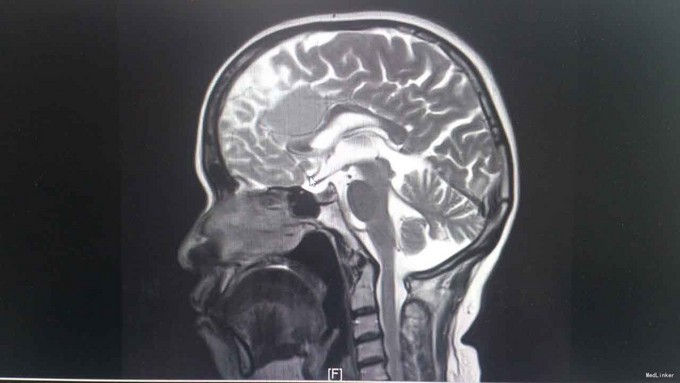

T:37℃,R: 20次/分,P:84次/分,BP:122/88mmHg。发育正常,营养中等,自主体位,步态平稳,表情自如,神志清楚,对答切题,查体合作。皮肤粘膜未见苍白、黄染,未见皮疹,无皮下出血点,无伤口。全身浅表淋巴结未扪及肿大。头颅无畸形。眉毛无脱落,眼睑无水肿、下垂、倒睫,睑结膜无苍白、充血,球结膜无充血、水肿,巩膜无黄染,角膜透明,眼球活动灵活,无凸出、凹陷、震颤、运动障碍,双侧瞳孔等大等圆,直径约3mm,对光反射灵敏,集合反射正常,左眼不能正常闭合。耳廓正常,无畸形,鼻部外形无异常,口唇红润,口腔粘膜未见出血点及溃疡,伸舌左偏,咽部无充血,扁桃体无肿大。颈软,无抵抗,颈静脉无充盈,肝颈静脉回流征(-),气管居中,甲状腺不大。胸廓对称无畸形、无局部膨隆或凹陷。呼吸平稳,节律规则。双侧呼吸动度对称。双肺部叩诊清音。双肺呼吸音清,未闻及干湿性啰音。心界不大,心率84次/分,律齐,各瓣膜区未闻及病理性杂音。腹平软,未及压痛,未及反跳痛,腹部未扪及包块,肝右肋下、剑突下未及,脾未触及,胆囊未触及,Murphy征(-)。移动性浊音阴性,肠鸣音正常,约4次/分。脊柱四肢无异常。生理反射存在,病理反射未引出。 专科检查:计算力、定向力、记忆力正常,双侧瞳孔等大等圆,直径约 4mm,对光反射灵敏,辐辏反射正常,眼球运动无受限,左侧眼睛不能正常闭合,左侧额纹消失,左侧鼻唇沟变浅,伸舌左偏,鼓腮无漏气,双上肢肌力5级,双下肢肌力5级,生理反射存在,病理反射未引出。 相关检查:血常规、大便常规、肝功能、凝血四项、离子四项、心肌酶、血脂四项、肾功能、肿瘤二项未见明显异常。 头颅增强MR1.左侧额叶大脑镰旁见团块状异常信号影,考虑脑膜瘤;2.双侧辐射冠区缺血灶;3.轻度脑萎缩。 肝胆脾胰B超、泌尿系B超未见异常。胸片示:1.双肺纹理稍增多、增粗,请结合临床;2.右上纵隔增宽,建议必要时CT检查。

诊断:脑膜瘤 治疗:甘露醇、地塞米松降颅压,择期手术治疗。